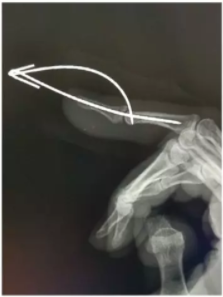

13、克氏针羊角钩技术修复伸肌腱

弯曲的克氏针被用于修复伸肌腱。首先将肌腱及缝线穿过骨隧道,当缝线穿出皮肤后就可以固定在弯曲的克氏针上面。